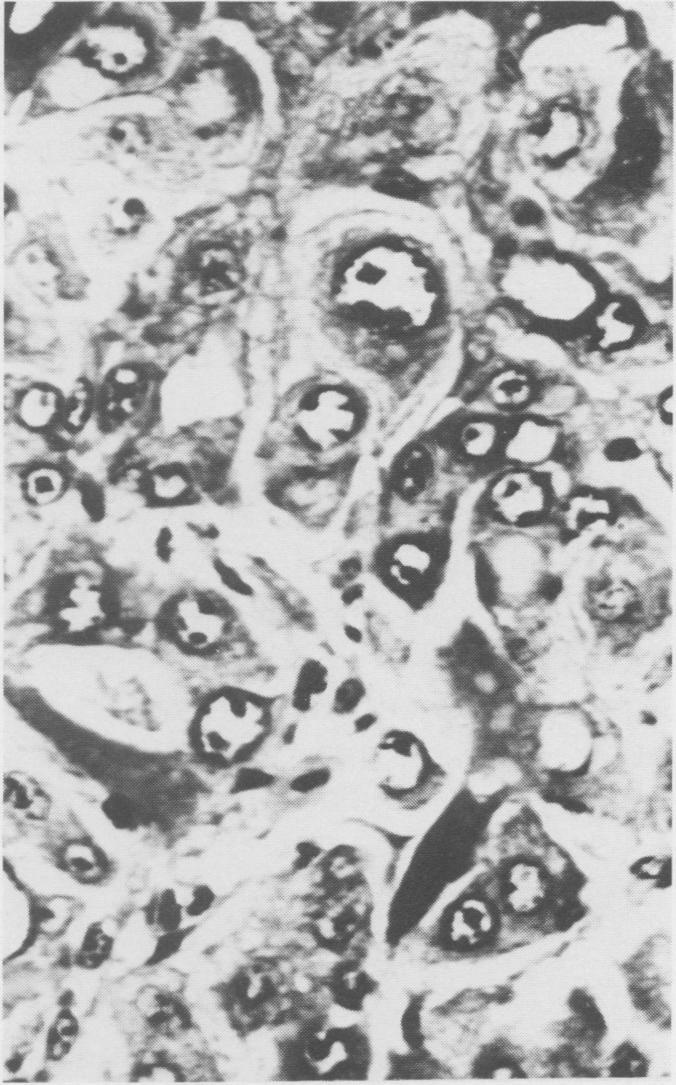

Eight bovine, two ovine and one porcine primary hepatocellular neoplasms were found during a five year survey of tumors from meat packing plants. The tumors varied in size and usually were yellow-grey. Some were encapsulated and divided into lobules by fibrous septa. The tumor cells closely resembled normal hepatocytes and were arranged in a trabecular pattern or in sheets with caverns or were a mixture of the two. Eosinophilic intranuclear inclusions were present in one bovine and one ovine case.